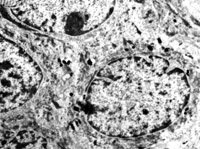

5-2-2 傷后第1天,毛細(xì)血管內(nèi)皮細(xì)胞核固縮,管腔內(nèi)血液凝集和瘀滯  TEM×6000